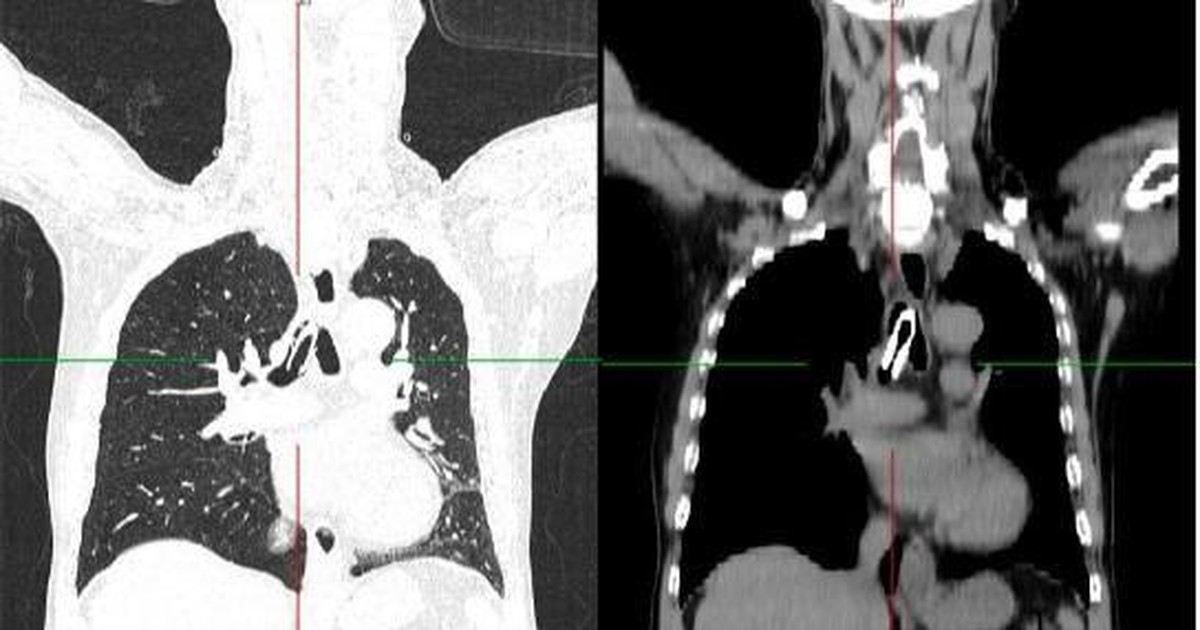

Chụp cắt lớp vi tính ngực có dựng hình khí phế quản cho thấy hình ảnh dị vật dạng ống trong khí quản và phế quản gốc, tắc hoàn toàn khí quản phía trên lỗ mở khí quản.